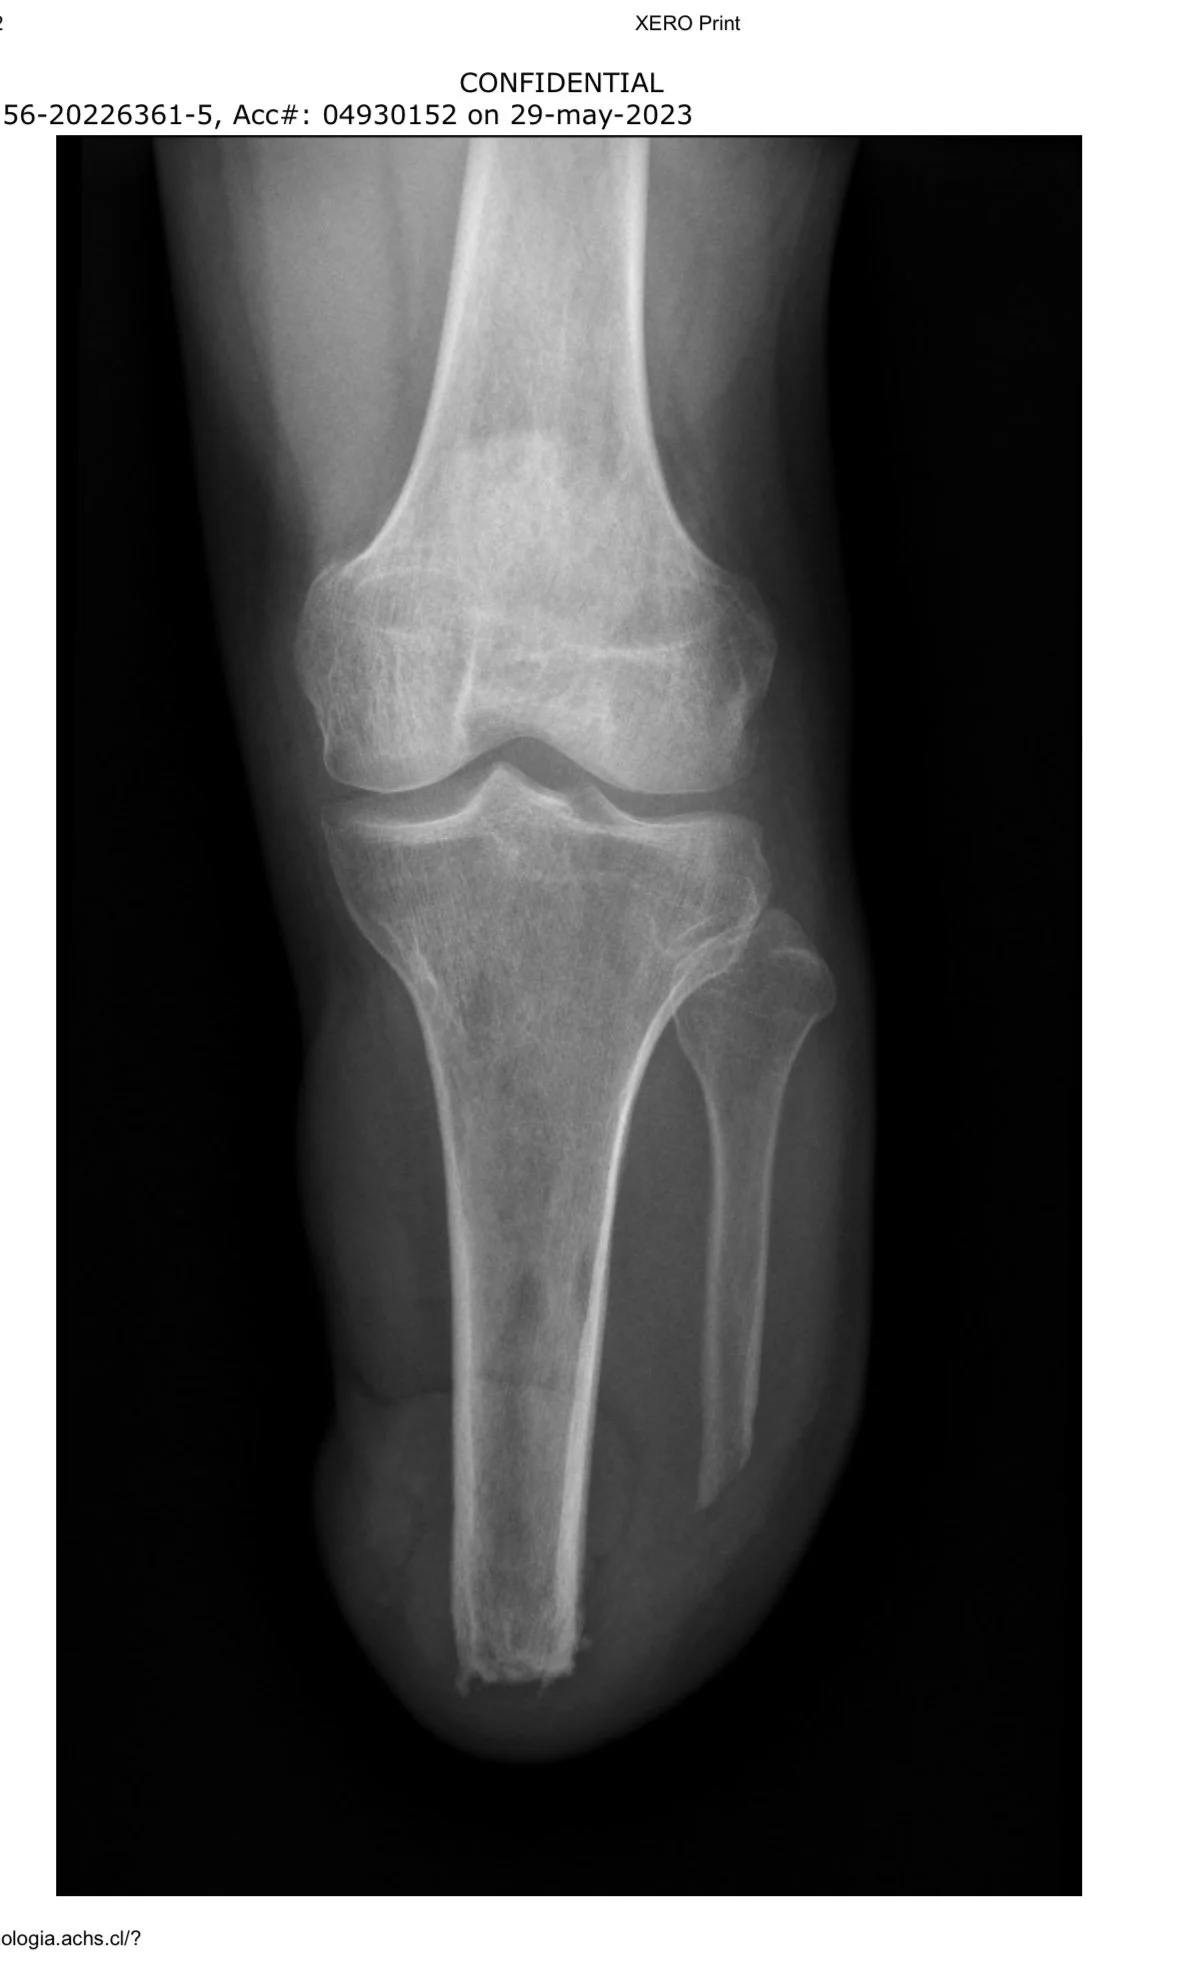

Desperté en una pieza blanca, con frío en las manos y un silencio que no se parecía a nada. Había entrado al pabellón con dos piernas; salí con una menos y una certeza incómoda: todo lo que yo creía estable se había ido al piso.

La prótesis llegó como un proyecto técnico, no como milagro. Molde, prueba, ajuste, herida, otro ajuste. Liner, medias, encaje, click. Aprendí dónde presionaba, dónde quemaba, qué pasaba cuando no la cuidaba. Me volví minucioso: crema tal hora, limpieza tal otra, revisión de tornillos, registro de roces. Si algo fallaba, lo corregía. Si no había corrección, lo sacaba del plan.